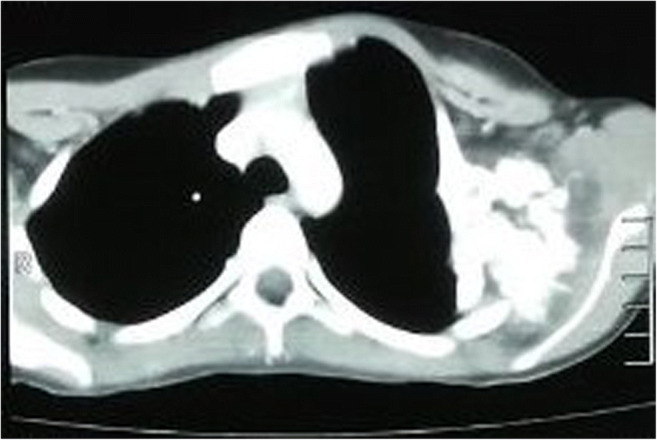

In December 2016, a 12-year-old female child presented to our hospital with a swelling in the upper anterolateral aspect of the left chest wall. On clinical examination, it showed as a firm swelling of about 7 × 4 cm over the anterolateral aspect of left chest wall at the level of sternal angle starting from left parasternal level and extending up to left anterior axillary line. The mass was having an irregular surface on palpation. The overlying skin was normal and temperature was also normal on palpation. On deep palpation, it was tender. On chest X-ray and CECT, it was diagnosed to be a case of periosteal chondroma with dimensions of 6.7 cm × 8 cm × 6.4 cm arising from the second rib. Chest X-ray showed a heterogeneously calcified lesion involving the left chest wall, causing cortical scalloping of the left first and second ribs, with multiple foci of ring and arc calcification and associated periosteal reaction. It did not seem to communicate with the medullary cavities of adjacent tubular bones as showed by CT imaging. CT also gave a better idea of scalloped cortex and matrix calcification (Fig. 1).

Fig. 1.

CT image showing heterogeneously calcified lesion with scalloped cortex and matrix calcification